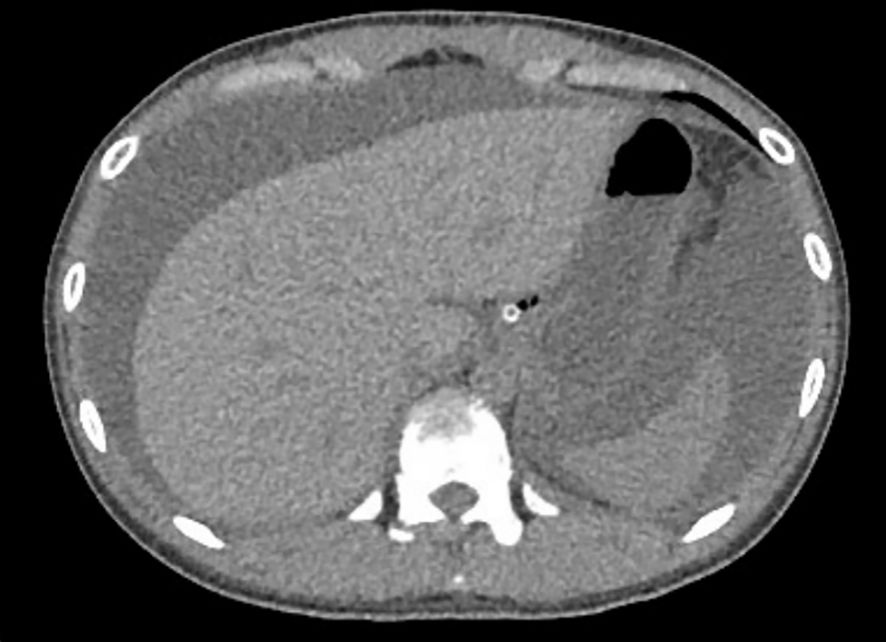

Based on the patient’s history of urticaria, abdominal urticaria was initially considered at that time. We used the hormone methylprednisolone succinate sodium (40mg qd) for anti-inflammatory and immune suppression, in combination with diphenhydramine to suppress immune related diseases in urticaria. However, abdominal pain persisted. CT re-examination results showed a large amount of ascites (Figure 3), indicating rapid disease progression. Besides, pleural effusion was present bilaterally. We increased the dosage of methylprednisolone sodium succinate to 120mg/day. On the same day, 1900ml of pale red bloody ascites was drained (exudate, without bacteria or clots). Analysis of the ascites revealed total protein 37.9 g/L, and concurrent serum total protein was 54.3 g/L, resulting in a Serum-Ascites Albumin Gradient (SAAG) of 16.4 g/L and an ascites-to-serum protein ratio of 30.2%. Since an SAAG >11 g/L indicates transudative ascites (typically associated with non-inflammatory causes such as cirrhosis, rather than inflammatory conditions like tuberculous peritonitis), this patient’s ascites was classified as transudative. Follow-up CT showed increased ascites, worsening intestinal edema, and dilatation with gas accumulation. Based on the 2019 EULAR/ACR Classification Criteria for SLE (Supplementary Figure S1), the patient scored 15 points (fulfilling the entry criterion of positive ANA and additive criteria including hematologic abnormalities, low complement, and SLE-specific antibodies). We considered the diagnosis of SLE. The patient was transferred to the Department of Rheumatology for specialized SLE management. But on rheumatology examination, no classic SLE stigmata (malar rash or discoid lesions) were noted, and severe epigastric pain and abdominal distension persisted. Liver function tests showed elevated alanine transaminase (50 U/L) and decreased total protein (43.8 g/L). Treatment was escalated to 20% human albumin (10 g/day) for hypoalbuminemia, followed by high-dose methylprednisolone pulse therapy (500 mg/day for 3 days) with supportive care (hepatoprotection, antibiotics, electrolyte correction).

Figure 3. Re-examination of abdominal computed tomography scan (Sept 1st, 2024). A large amount of ascites, which has increased compared to before. Widespread thickening and edema of the abdominal intestinal wall.